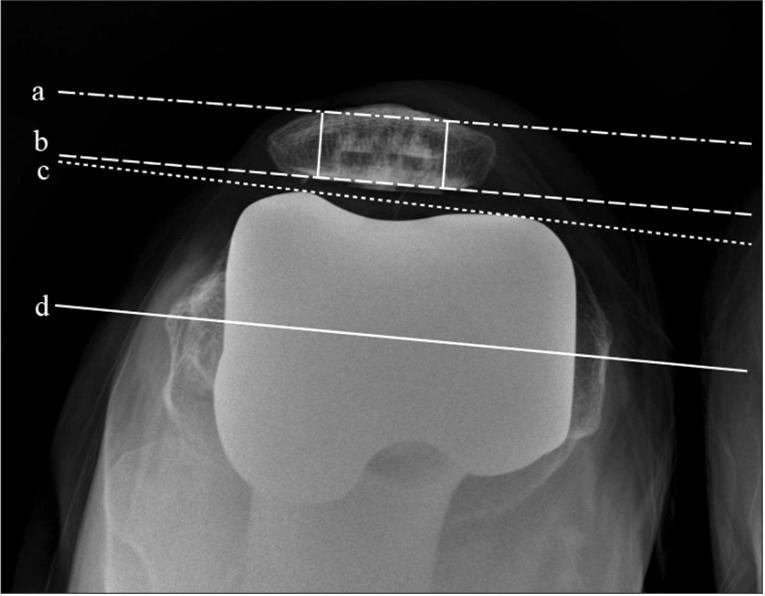

A total of 56 patients (76 knees) who underwent TKA using Advance Medial Pivot Knee system between May 2009 and April 2011 and were available for minimum 1-year follow-up were enrolled in this study. Whiteside's line and the transepicondylar line were used to determine the rotational alignment of the femoral component. Patella cut was aimed to be parallel to the anterior patellar cortex during surgery. Radiographic evaluation was performed using plain axial radiographs. The rotational alignment of the femoral component was measured as the angle between the anterior condylar axis and the surgical transepicondylar axis. The patellar resection angle was measured between the patellar resection axis and the anterior cortical line of the patella. Patellar tilt was evaluated to investigate the correlation with the rotation of the femoral component and patellar resection angle.

本研究纳入了2009年5月至2011年4月间使用Advance Medial Pivot Knee系统接受TKA且至少有1年随访资料的56例患者(76膝)。采用Whiteside线和经髁间线来确定股骨组件的旋转对线。手术中髌骨截骨旨在使其与髌骨前皮质平行。使用普通轴向X线片进行影像学评估。股骨组件的旋转对线通过前髁轴与手术经髁间轴之间的角度来测量。髌骨切除角度在髌骨切除轴与髌骨前皮质线之间测量。评估髌骨倾斜以研究其与股骨组件旋转及髌骨切除角度的相关性。